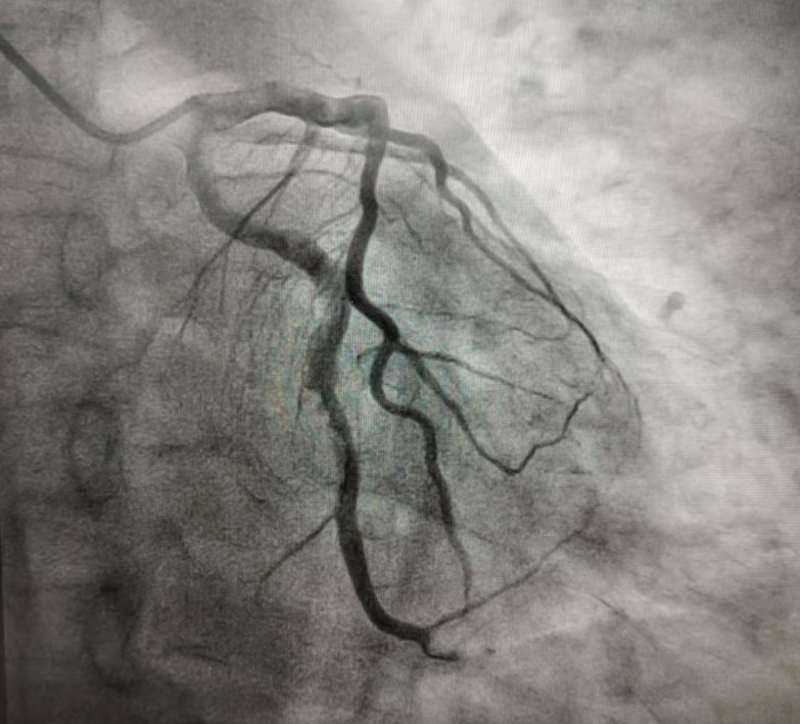

2024年10月的某天,患者程某某因胸闷两天,前来惠州市中心人民医院中文博彩平台分院(中文博彩平台人民医院)心血管内科就诊。经诊查,诊断为冠心病、急性非ST段抬高型心肌梗死 KillipI级,GRACE评分122分,危险分层高危。行冠脉造影示回旋支远段近端见大量血栓影、狭窄90%,远段远端见大量血栓影、狭窄100%闭塞,前向血流TIMI0级(图1)。心血管内科团队予为患者行PTCA和血栓抽吸术,复查造影显示:回旋支远段近端血栓无变化,远段远端血栓消失(图2)。考虑血栓负荷重,回旋支远段近端暂不宜行支架置入术,拟给予抗栓治疗后择期复查冠脉造影。

(图2)